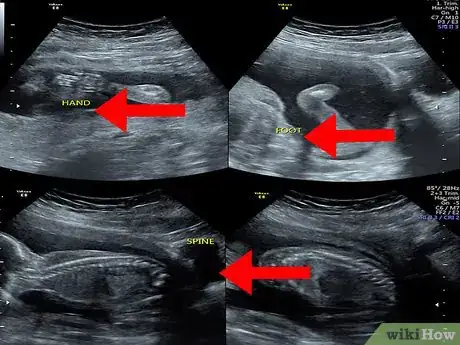

Spot the baby. Your baby will also look grey or whitish and will be located within the amniotic fluid (the dark area inside of the womb). Look at the area within your amniotic fluid to try to make out the outline and features of your baby.

• The details that you see in the image will depend on the stage of your pregnancy. For example, at eight weeks, the fetus will look something like a gummy bear or a baked bean; at 12 weeks, you may only be able to identify the head of your baby; while at 20 weeks, you may be able to see the spine, eyes, feet, and heart.[8]